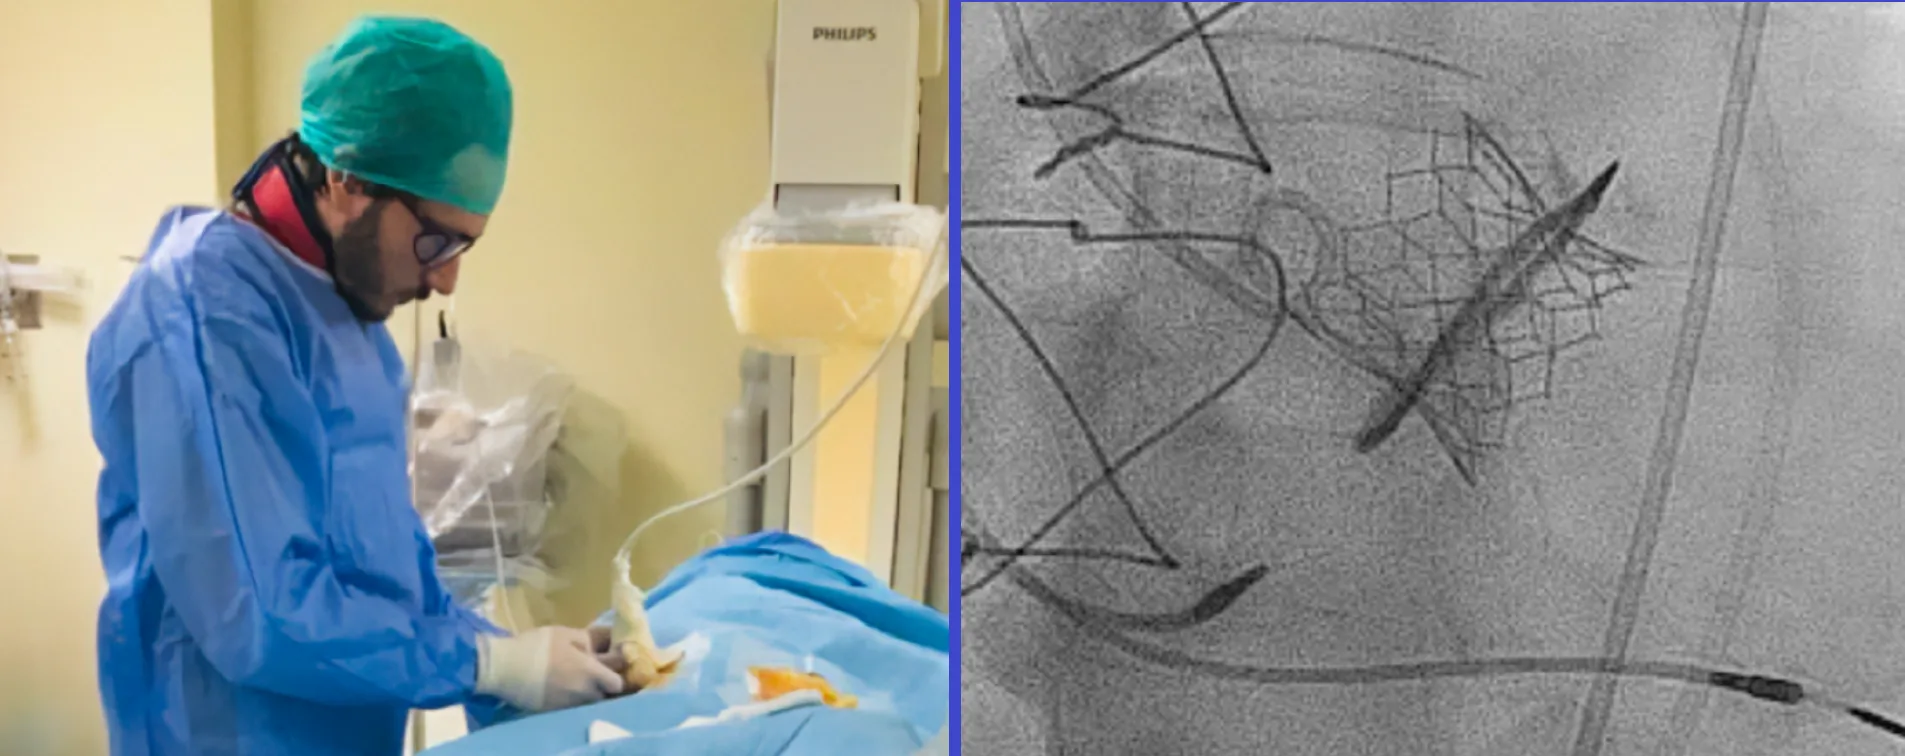

Ο Δρ. Ανδρέας Τριανταφύλλης είναι Επεμβατικός Καρδιολόγος, με ενεργή παρουσία στα Αιμοδυναμικά Εργαστήρια των Νοσοκομείων Mediterraneo, Μητέρα (Όμιλος Υγεία) και Γ.Ν. Ασκληπιείο Βούλας (θέση: Επιμελητής Α’). Έχει διατελέσει Επικεφαλής Επεμβατικής Καρδιολογίας (Chef de Clinique Interventie Cardiologie) στο διεθνώς αναγνωρισμένο Νοσοκομείο Catharina Ziekenhuis Eindhoven (Ολλανδία).

Η μετεκπαίδευσή του στην Επεμβατική Καρδιολογία, με έμφαση στη διαδερμική αντιμετώπιση σύνθετων στεφανιαίων βλαβών και στη διακαθετηριακή αντικατάσταση αορτικής βαλβίδας (TAVI/TAVR), πραγματοποιήθηκε σε κορυφαία ευρωπαϊκά κέντρα: St. Antonius Ziekenhuis Nieuwegein (Ολλανδία), Universitaire Ziekenhuizen Leuven (Βέλγιο) και Catharina Ziekenhuis Eindhoven (Ολλανδία).